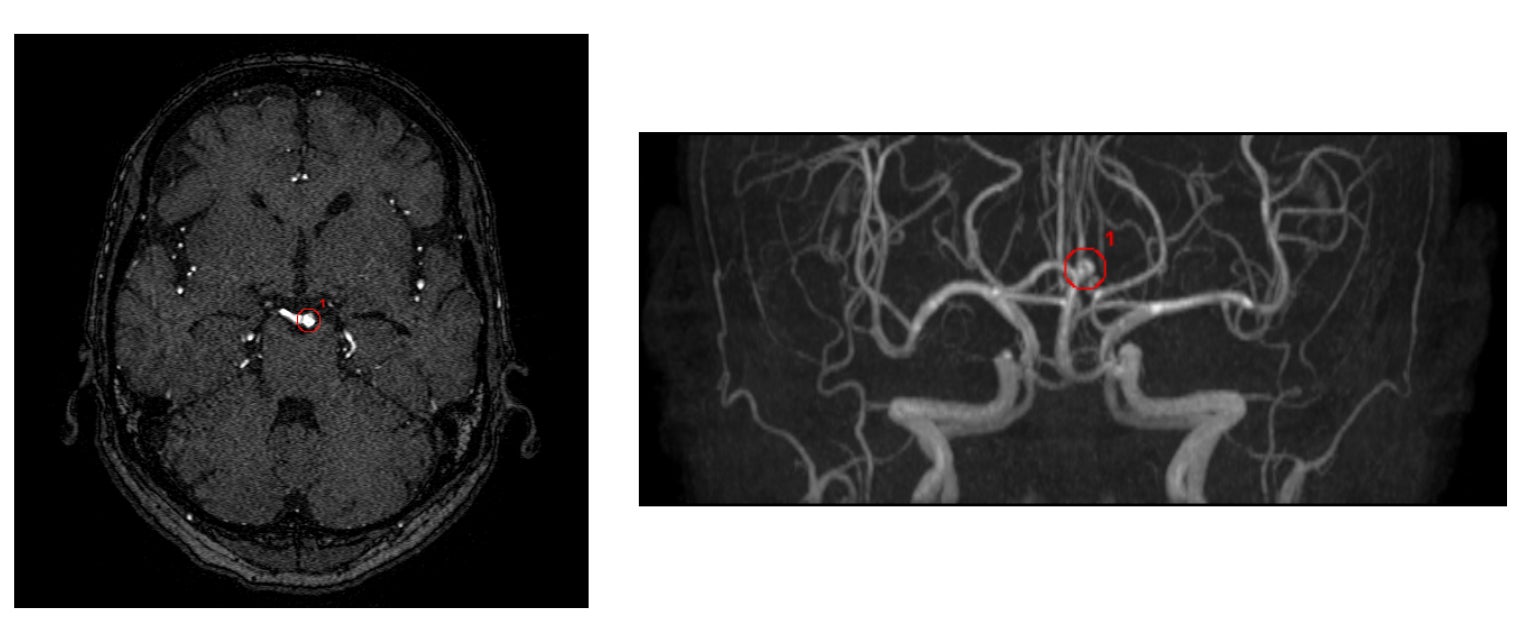

・脳底動脈の検出事例

※いずれの検出例もイメージであり、実際の製品表示とは異なる場合があります。

EIRL Brain Aneurysでは、脳動脈瘤の候補点について1症例あたり最大4つを検出し、表示します。今回、一部変更申請を取得した新バージョンでは感度92.3%、1症例あたりの偽陽性の検出数が「1」以下となりました。

新モデルでは、学習データの追加学習に加えてアルゴリズムの見直しを行うことで、検出感度を維持しながら、症例あたりの平均偽陽性数を「1」以下となるよう改善を行いました。